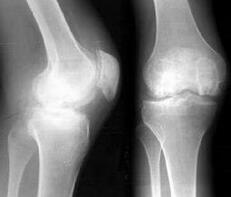

從不同部位病理性增生辯證康復,力求從根源上進行徹底鏟除。康復效果在現代醫學影像學下印證增生縮小,甚至消退,及功能與機能恢復全過程。絕大多數的增生是生理性增生,對穩定局部關節有益、是...